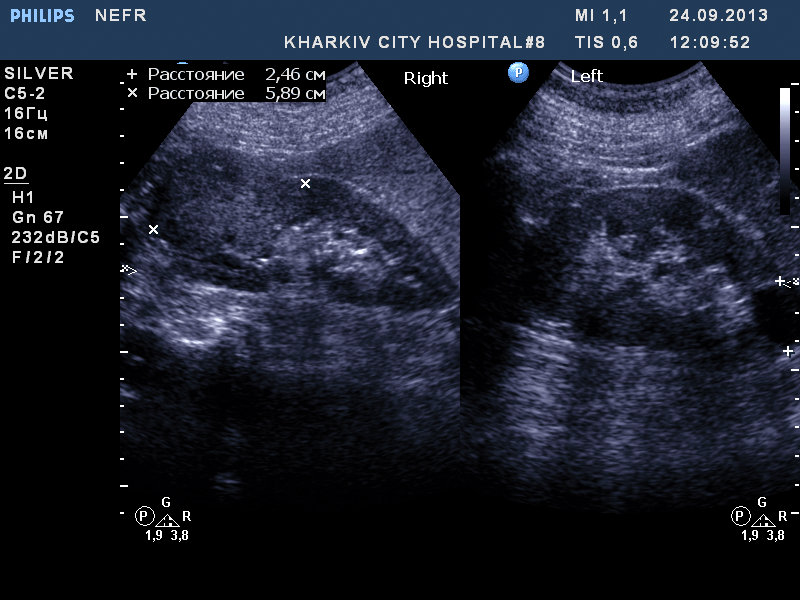

Пациентка 76 лет. Образование правой почки. Вероятно ПКР. Рекомендовал КТ и консультацию уролога.

1.jpg